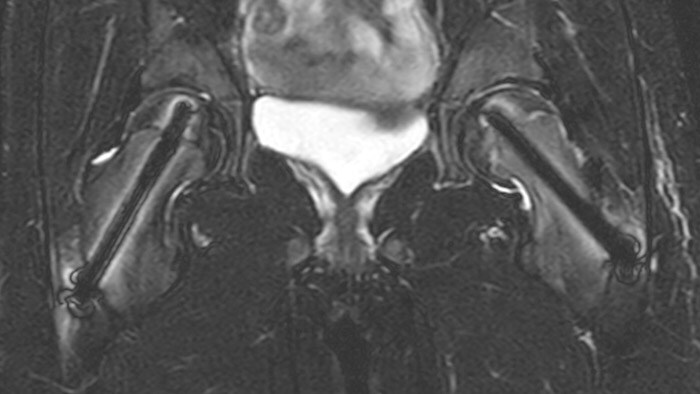

Crohn’s disease in the terminal ileum A large abscess is visible near the terminal ileum, in the middle of the coronal image.